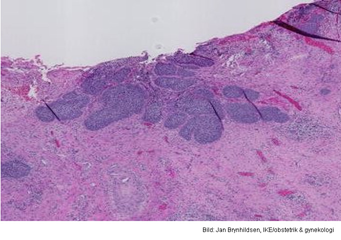

Vad visar bilden?

Cervixcancer

Invasivt växande skivepitelcancer.